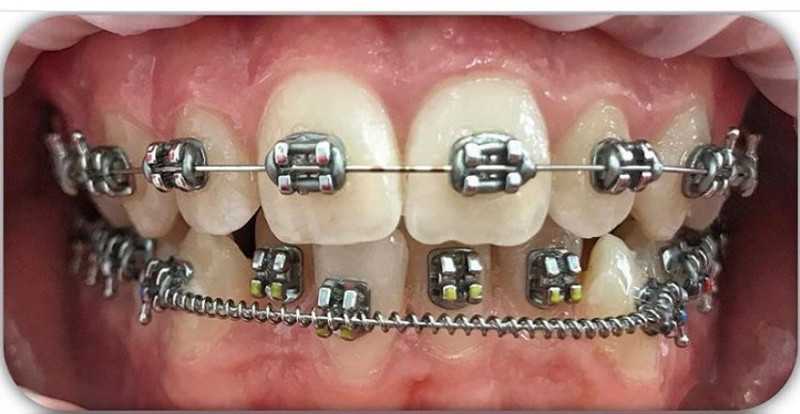

Установка брекетов

В данном случае установлена система Marquis.

Скученность и нарушения прикуса были "до", которые могут привести к массе проблем с зубами и суставом. И на фото "после" мы видим результат, скученность ушла, прикус практически правильный. Осталось немного и будет идеальный результат.

Между фото "до" и "после" прошло 9 месяцев.